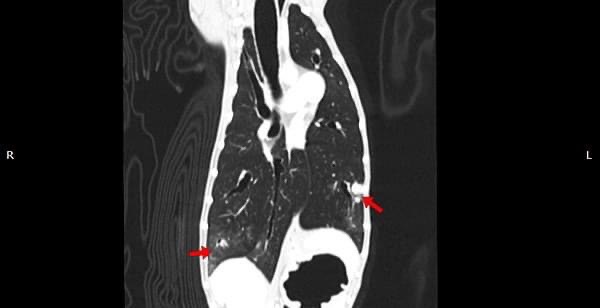

狗狗的慢性鼻炎維持3-4個月,越來越嚴重,他院轉診至築心,經由內視鏡+電腦斷層確認為鼻腔上皮癌,而且由於病程時間長,已經轉移至胸腔,代表壽命不長了,至少家人心中有個答案,有心理準備陪狗狗最後一段路。